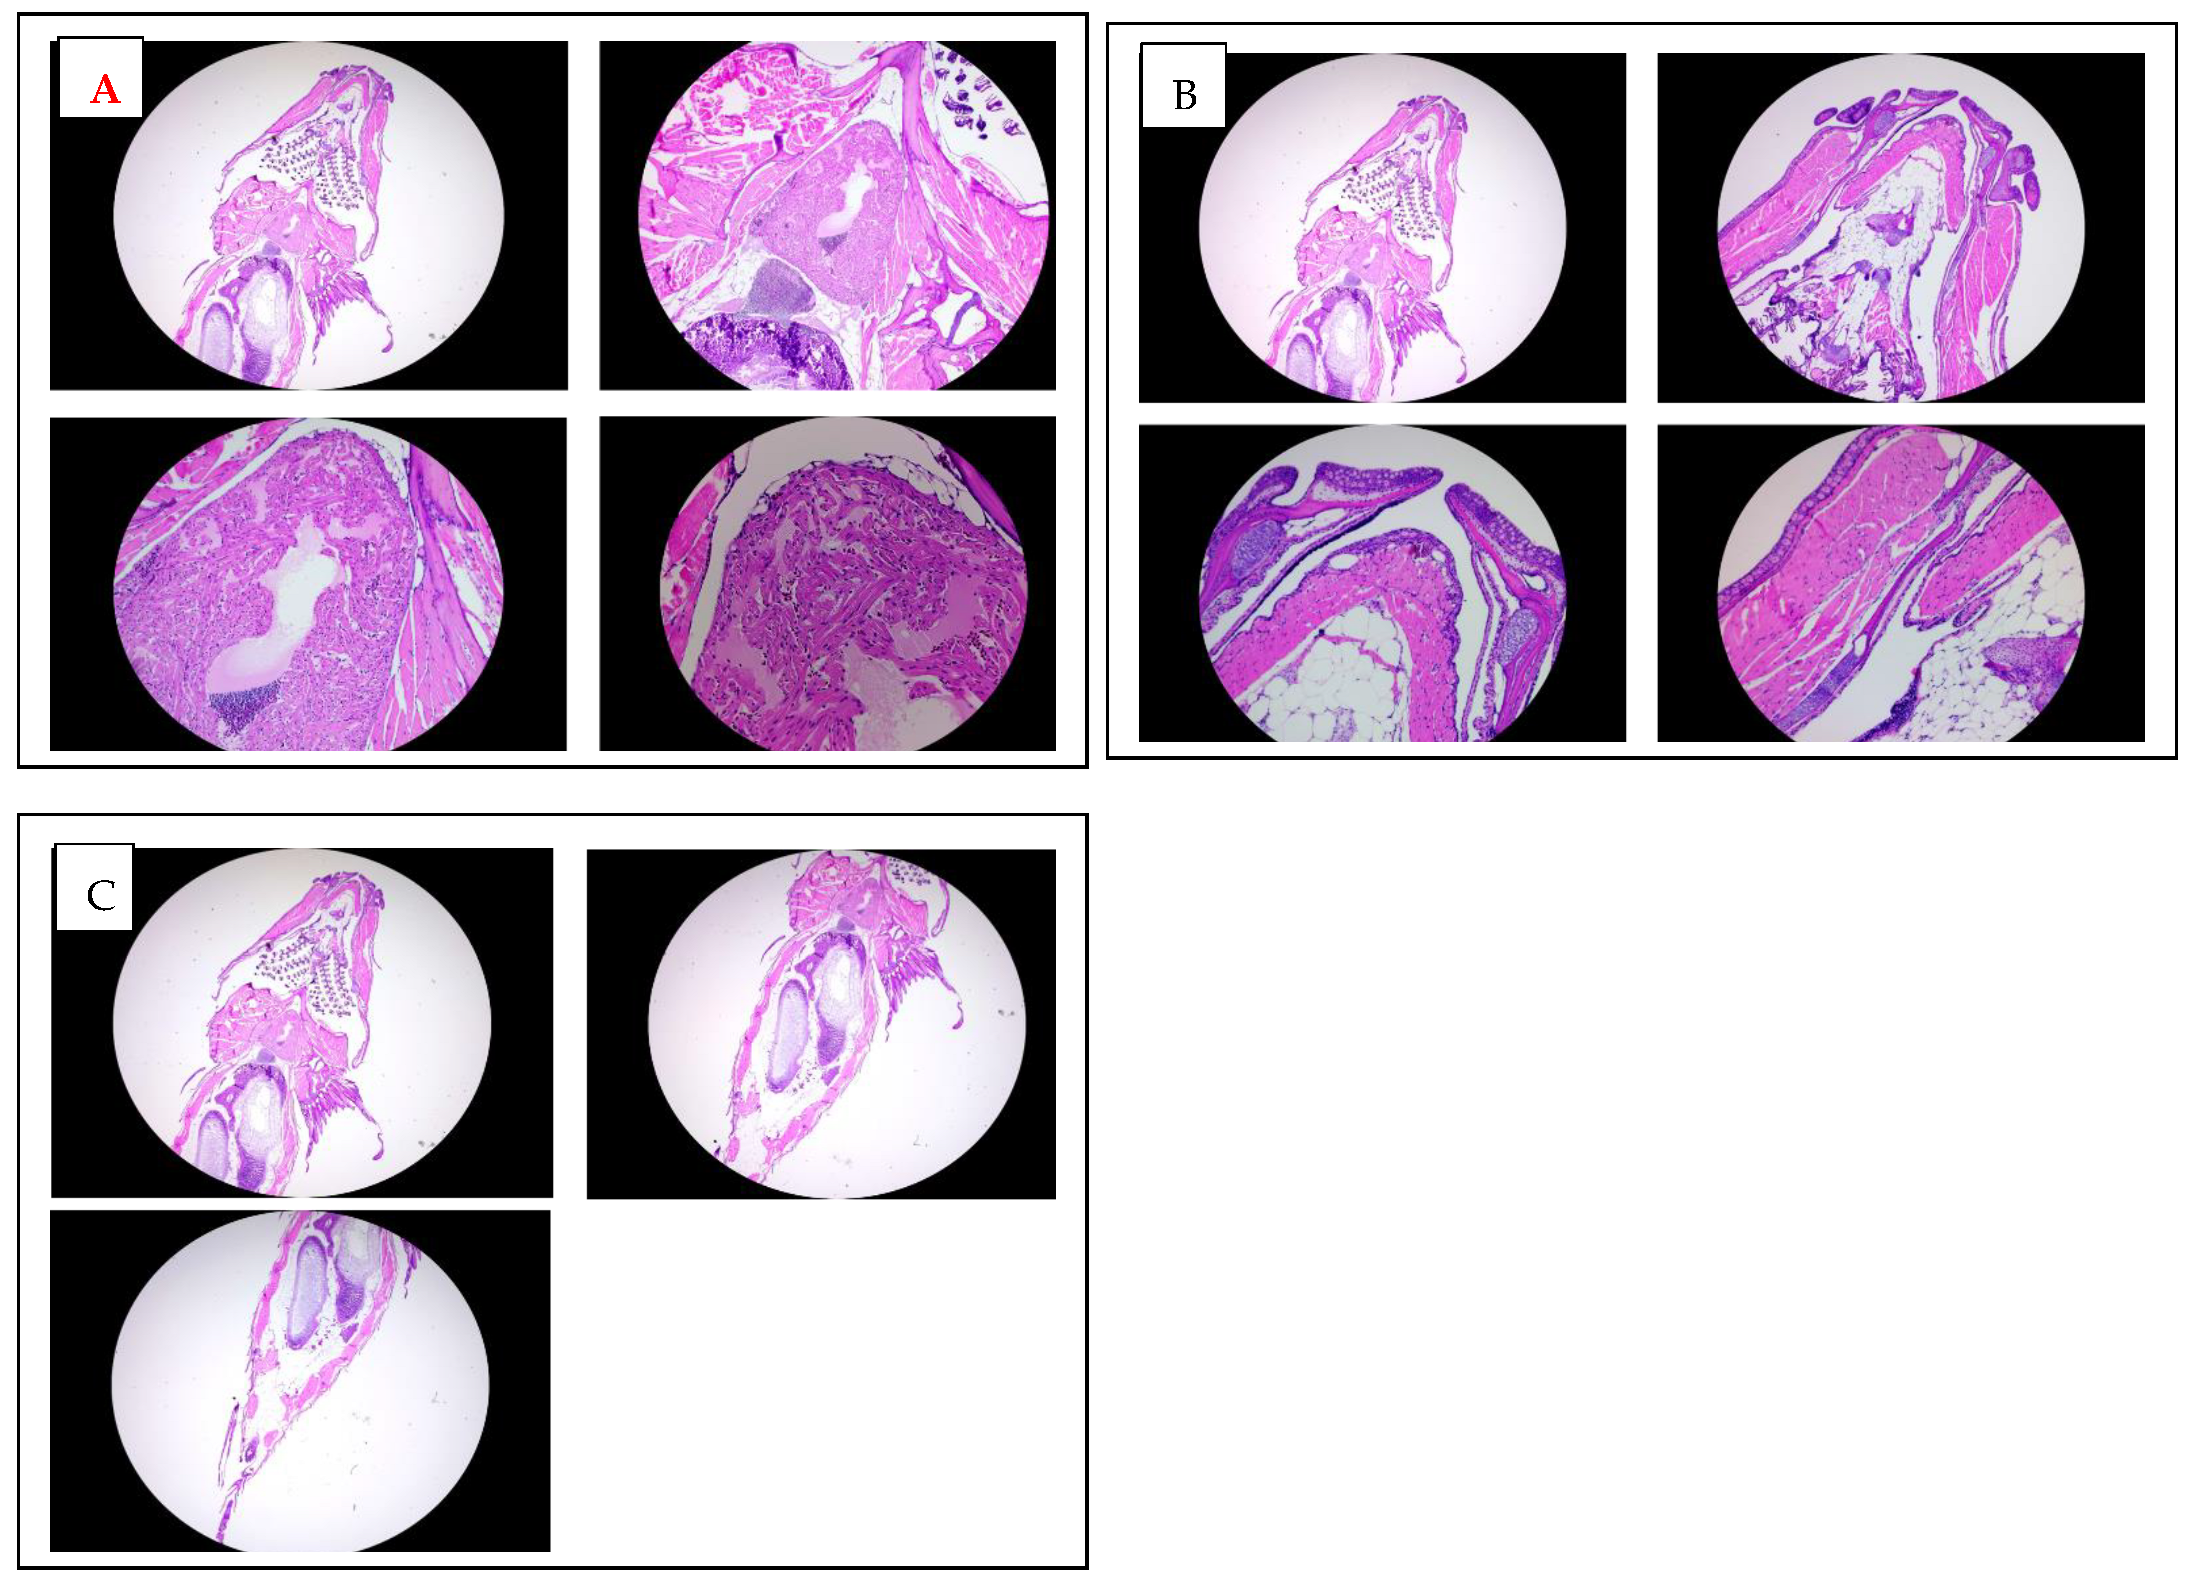

3.5. Histological Evaluation of K21-Treated Adult Zebrafish

A histological analysis of adult zebrafish treated chronically with K21 was performed to examine potential changes in the tissue structure and integrity. Hematoxylin and eosin-stained sections from the anterior (heart region; Figure 5A) and posterior (abdominal region; Figure 5B) areas of adult zebrafish were evaluated microscopically at multiple magnifications (2×, 5×, 10×, and 20×).

An examination of the heart region in adult zebrafish revealed intact myocardial structures with clearly defined cardiomyocytes arranged regularly around the heart chambers. There were no evident morphological abnormalities or signs of cardiotoxicity in the treated fish compared to controls. Similarly, histological sections of the abdominal region demonstrated a normal architecture and cellular integrity of internal organs such as the liver, gastrointestinal tract, and surrounding musculature, with no apparent pathological features or inflammatory cell infiltration observed.

Overall, these histological findings indicate that chronic exposure to K21 at the established optimal concentration (1 µL/L) does not adversely impact organ morphology or tissue integrity. Instead, the maintained histological integrity of essential organs, combined with the observed growth enhancement at macroscopic levels, supports the safety and potential physiological benefits of K21 treatment. This further underscores the suitability of K21 as a candidate for biomedical applications and growth enhancement strategies in aquaculture.

Histological analysis of adult zebrafish treated with K21. (A). Hematoxylin and eosin (H&E) staining of transverse sections through the anterior heart region of K21-treated adult zebrafish at increasing magnifications (2×, 5×, 10×, and 20×). The cardiac chambers surrounding myocardial tissue, and adjacent vasculature appear structurally intact, with no signs of fibrosis, inflammation, or pathological remodeling. (B). H&E staining of transverse sections of the mouth and jaw area up to trunk region of K21-treated adult zebrafish at 2×, 5×, 10×, and 20× magnifications. (C) H&E staining of transverse sections through the posterior abdominal region to the tail area of K21-treated adult zebrafish at 2×, 5×, 10×. The abdominal cavities, including the digestive tract, musculature, and associated organs, exhibit a normal histological architecture with no apparent abnormalities or inflammatory cell infiltration. These findings indicate that chronic K21 exposure does not induce histopathological alterations in the heart or abdominal organs, supporting its safety in long-term applications.